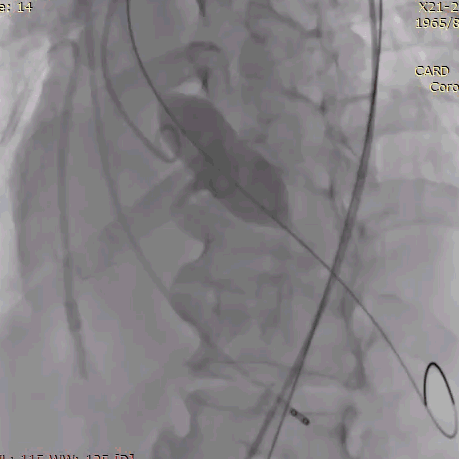

植入前冠脉造影

主动脉根部造影

直头导丝跨瓣

20mm球囊预扩

冠脉保护支架植入

AV23瓣膜释放到工作位

瓣膜完全释放

冠脉支架释放

植入后造影